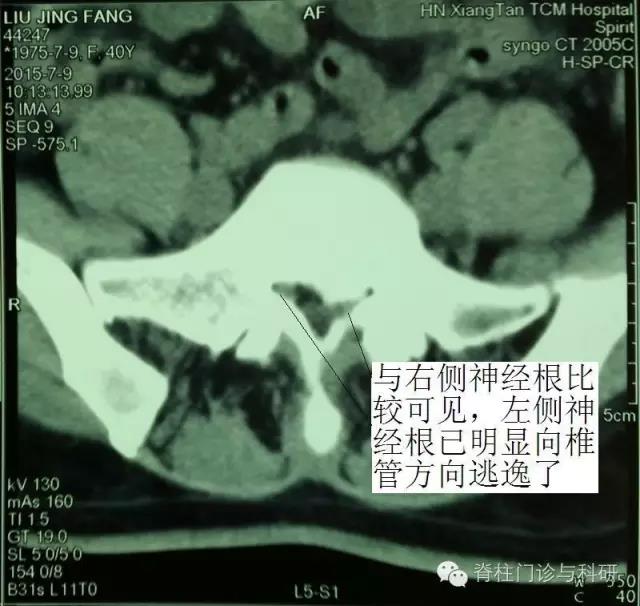

先看看这位典型病例的影像学资料:

这是湘潭市中医医院脊柱骨科门诊一位中年女士的腰椎间盘CT,她5年前有L5/S1椎间盘明显突出症病史,当时出现典型的左下肢明显麻痛症状,但经保守治疗和康复锻炼后,5年来一直未复发。

那疑问点来了:L5/S1明显突出,为什么近5年能近乎临床痊愈呢?仔细阅片可知,L5/S1左侧神经所在的侧隐窝明显狭窄,但神经根的位置已明显向椎管方向移位了,这是典型的受压神经根的自我逃逸!因为5年前的那次发病,受压的神经根可谓处于水深火热之中,但剧烈疼痛后,神经根变“聪明”了,显然已从严重狭窄的侧隐窝向椎管方向逃逸,采取了“惹不起便躲起”的“自愈”政策。